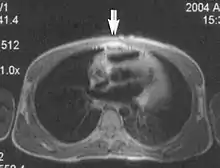

Metal artifacts

Metal artifacts occur at interfaces of tissues with different magnetic susceptibilities, which cause local magnetic fields to distort the external magnetic field. This distortion changes the precession frequency in the tissue leading to spatial mismapping of information. The degree of distortion depends on the type of metal (stainless steel having a greater distorting effect than titanium alloy), the type of interface (most striking effect at soft tissue-metal interfaces), pulse sequence and imaging parameters. Metal artifacts are caused by external ferromagnetics such as cobalt containing make-up, internal ferromagnetics such as surgical clips, spinal hardware and other orthopaedic devices, and in some cases, metallic objects swallowed by people with pica.[3] Manifestation of these artifacts is variable, including total signal loss, peripheral high signal and image distortion (Figs 3 and 4).[1] Reduction of these artifacts can be attempted by orientating the long axis of an implant or device parallel to the long axis of the external magnetic field, possible with mobile extremity imaging and an open magnet. Further methods used are choosing the appropriate frequency encoding direction, since metal artifacts are most pronounced in this direction, using smaller voxel sizes, fast imaging sequences, increased readout bandwidth and avoiding gradient-echo imaging when metal is present. A technique called MARS (metal artifact reduction sequence) applies an additional gradient, along the slice select gradient at the time the frequency encoding gradient is applied. ==Signal processing dependent artifacts== The ways in which the data are sampled, processed and mapped out on the image matrix manifest these artifacts.[1]